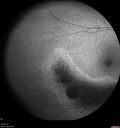

Sectoral Retinitis Pigmentosa - Asymptomatic232 views56-year-old female - The patient was in for an annual checkup because of her diabetes. No visual complaints (no night vision trouble)

293 Invitae genetic panel - negative     (0 votes)